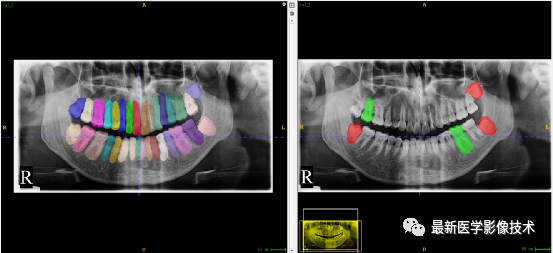

验证集牙齿分割计数和异常牙齿分割识别

左图是分割计数,右图是异常牙齿分割识别结果